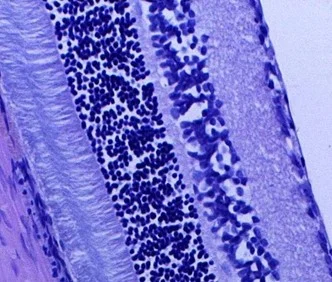

Гистологические методы оценки изменений сетчатки и зрительного нерва